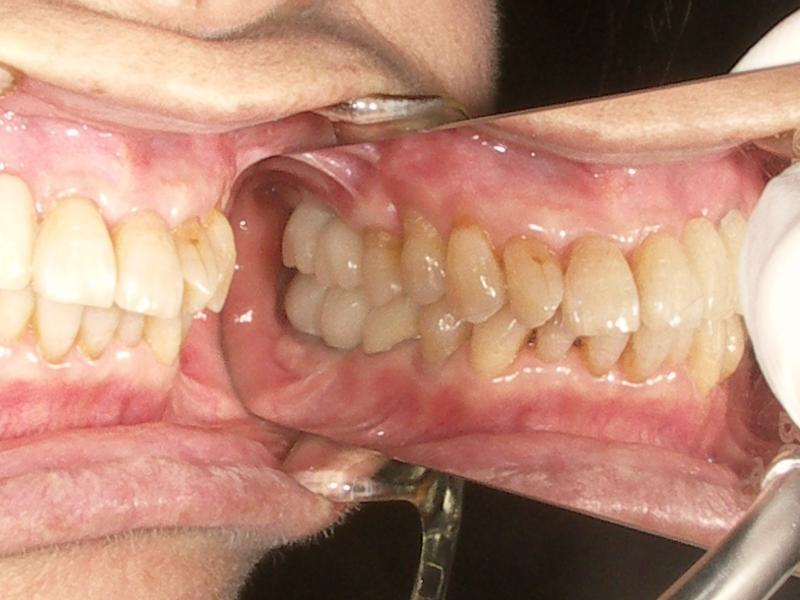

しかし、歯がなくなったところをそのまま放置していると、噛み合う反対の歯(下の歯が抜けているなら上の歯)が伸びてきてしまったり、後ろの歯がって前に倒れこんできたりしてしまいます。

そうなると噛んだ時にその場所が一番あたることになるのですが、ゆっくりと歯が移動していくこと、人間の慣れる能力が高いことから気がつかなかったり、知らず知らずのうちに噛む場所をずらしたりしてしまいます。そうすると別の場所が真っ先に当たるようになり(早期接触、咬頭干渉)、歯に小さな亀裂が入り虫歯になりやすくなったりと、ゆっくりと口の中全体を崩壊させていくことにつながってしまいます。

歯がなくなったところの隣の歯の10年後の生存率を調べた研究(残っているかどうか、虫歯になったとかは関係ない)では歯の欠損を放置した場合は81%という結果が出ています。

ちなみに部分入れ歯は56%、ブリッジは92%、インプラント100%という結果になっています。

こう見ると放置しても10年後に80%も隣の歯が残っているじゃないか、と思ってしまいそうですが、隣以外の歯にも悪影響があることを考えると、やはり欠損の放置というのはあまりにも危険なことかと思います。